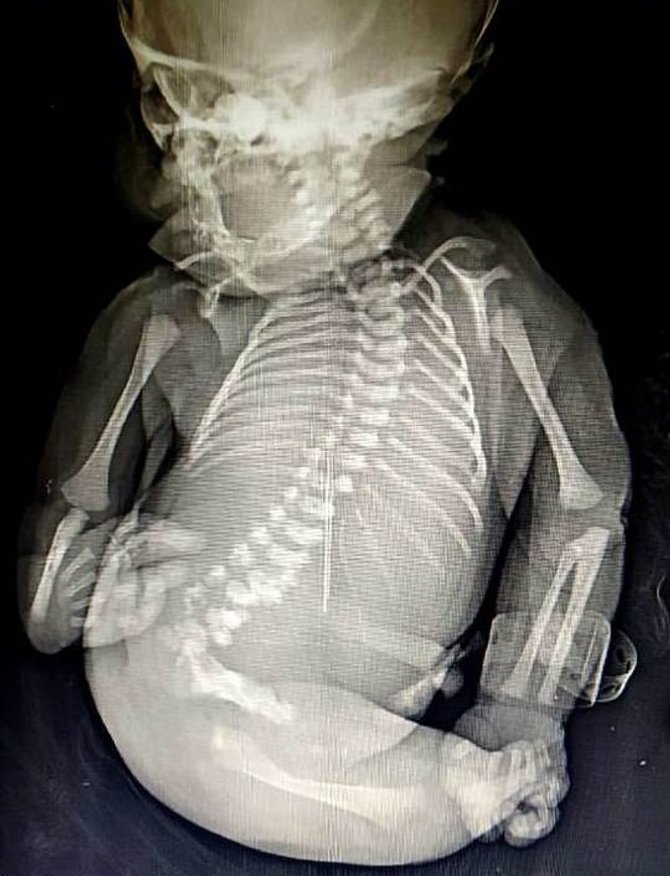

คุณแม่ยังสาวชาวอินเดียให้กำเนิดเด็กน้อยสุดพิเศษ "เงือกน้อย" ในภาวะ

Mermaid Syndrome ก่อนเด็กจะสิ้นลมหายใจไปเพียง 15 นาทีให้หลัง

เนื่องจากเด็กคนนี้เกิดมาพร้อมกับสภาพร่างกายที่ไม่สมบูรณ์แบบ

เนื่องจากไม่มีส่วนท่อนขาเหมือนกับเด็กทารกทั่วไป

ทำให้เด็กคนนี้ได้รับการขนานนามว่า "เจ้าเงือกน้อย"

เด็กแรกเกิดที่เป็นเจ้าเงือกน้อย หรือ Mermaid Syndrome

เป็นภาวะความผิดปกติของทารกในครรภ์

ที่มีอัตราความเสี่ยงหนึ่งต่อแสนคนในกลุ่มเด็กแรกเกิด